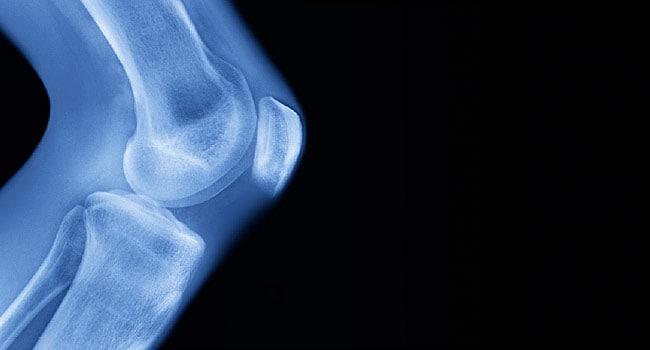

အရိုးထိပ်များကိုဖုံးအုပ်ထားသော အရိုးနုများပါလာသောအခါ အရိုး

နှင့်အဆစ်ရောင်ရောဂါဖြစ်ပွားသည်။ ထိုရောဂါသည်ကုသ၍မရနိုင်

သော်လည်း ဖြစ်ပွားသောလက္ခဏာများသက်သာ၍ ရောဂါတိုးတက်ဖြစ်ပေါ်လာမှုကို နှေးကွေးစေနိုင်သည့်နည်းလမ်း

များစွာရှိပြီး လေ့ကျင့်ခန်းများသည်လည်းတစ်ခုအပါအဝင်ဖြစ်သည်။